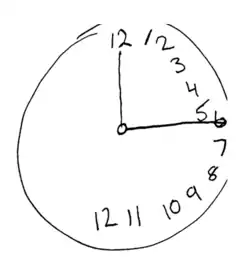

For example, a stroke affecting the right parietal lobe of the brain can lead to neglect for the left side of the visual field, causing a patient with neglect to behave as if the left side of sensory space is nonexistent (although they can still turn left). In an extreme case, a patient with neglect might fail to eat the food on the left half of their plate, even though they complain of being hungry. If someone with neglect is asked to draw a clock, their drawing might show only the numbers 12 to 6, or all 12 numbers might be on one half of the clock face with the other half distorted or blank. Neglect patients may also ignore the contralesional side of their body; for instance, they might only shave, or apply make-up to, the non-neglected side. These patients may frequently collide with objects or structures such as door frames on the side being neglected.[1]

Line cancellation neglect test result The Allochiria phenomena might be revealed by the request to draw a clock.

The Allochiria phenomena might be revealed by the request to draw a clock. The patients has to mark the half of the line.

In order to assess not only the type but also the severity of neglect, doctors employ a variety of tests, most of which are carried out at the patient's bedside. Perhaps one of the most-used and quickest is the line bisection. In this test, a line a few inches long is drawn on a piece of paper and the patient is then asked to dissect the line at the midpoint. Patients exhibiting, for example, left-sided neglect will exhibit a rightward deviation of the line's true midpoint.[6]

Visual neglect can also be assessed by having the patient draw a copy of a picture with which they are presented. If the patient is asked to draw a complex picture they may neglect the entire contralesional side of the picture. If asked to draw an individual object, the patient will not draw the contralesional side of that object.[14]